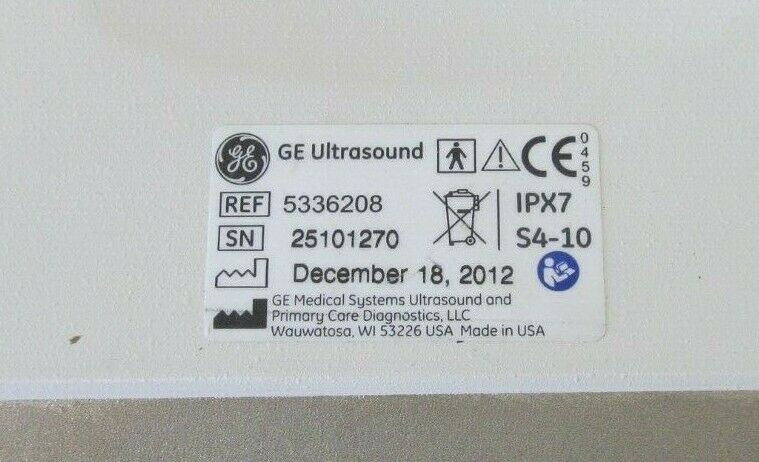

2014 GE L8-18i -RS probe for GE Ultrasound

Sale price$ 7,170.06